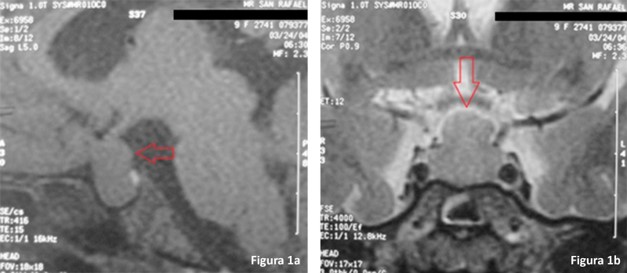

Síndrome de Van Wyk–Grumbach asociado a hiperplasia hipofisaria: reporte de caso y revisión de la literatura

Nelly Silva, Mauricio Coll, Romain Coll

31-34